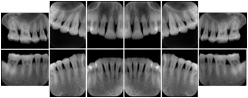

Intra-oral radiography typically involves acquisition of multiple images of various parts of the dentition. Many digital radiographic systems offer customized templates that are used for displaying the images in a study on the screen. These templates may also be referred to as mounts or view sets. The Structured Display Object represents a standard method of encoding and exchanging the layout and intended display of Structured Displays. A structured display object created in this manner could be stored with a study and exchanged with images to allow for complete reproduction of the original exam.

1. A patient visits a General Dentist where a Full Mouth Series Exam with 18 images is acquired. The dentist observes severe bone loss and refers the patient to a Periodontist. The 18 images from the Full Mouth Series along with a Structured Display are copied to a DICOM Interchange CD and sent with the patient to see the specialist. The Periodontist uses the CD to open the exam in his Dental Radiographic Software and consults via phone with the General Dentist. Both are able to observe the same exam showing the images on each user's display using the exact same layout.

Intra-oral Full Mouth Series Structured Display

Figure OO-1. Intra-oral Full Mouth Series Structured Display